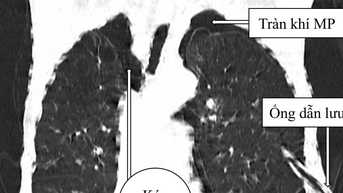

លទ្ធផលបានបង្ហាញថាអ្នកជំងឺមាន pneumothorax ទ្វេភាគី និងអាស៊ីតមេតាបូលីកធ្ងន់ធ្ងរ។

ប្រឈមមុខនឹងស្ថានភាពខាងលើ វេជ្ជបណ្ឌិតបានធ្វើការវះកាត់ pleurodesis ទ្វេភាគី ដើម្បីបញ្ចេញប្រហោង pleural ពីសម្ពាធដែលបណ្តាលមកពីការប្រមូលផ្តុំខ្យល់ ជួយឱ្យអ្នកជំងឺដកដង្ហើមបានស្រួល។